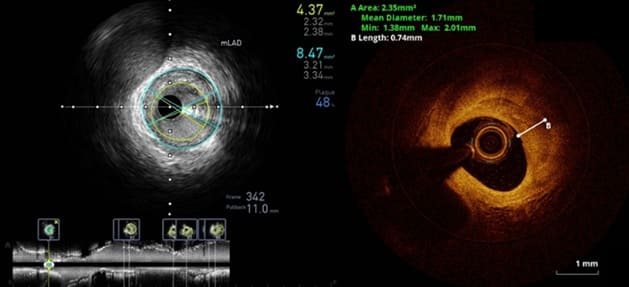

หากผลการฉีดสีสวนหัวใจพบความผิดปกติชัดเจน (เช่น หลอดเลือดตีบแคบมากกว่า 75%) สอดคล้องกับผลตรวจชนิดไม่รุกรานก่อนหน้าจะมีข้อบ่งชี้ในการทำหัตถการขยายหลอดเลือดหัวใจ แต่ก็มีหลายครั้งที่ผลการฉีดสีสวนหัวใจให้ผลก้ำกึ่ง ในกรณีเช่นนี้การตรวจเพิ่มเติมโดยใส่อุปกรณ์เข้าไปในหลอดเลือดหัวใจจะช่วยให้ได้ข้อมูลที่ละเอียดขึ้น เพิ่มประสิทธิภาพการรักษา ซึ่งการตรวจดังกล่าว ได้แก่ ส่องกล้องเพื่อสร้างภาพภายในหลอดเลือดหัวใจ (Intravascular Imaging) โดยใช้คลื่นเสียง (Intravascular Ultrasound : IVUS) หรือ คลื่นแสง Near Infrared (Optical Coherence Tomography : OCT) และการศึกษาความดัน/อัตราการไหลของเลือด เหนือและใต้ต่อรอยตีบ (Functional Assessment) เช่น การวัด Functional Flow Reserve (FFR) หรือ Instantaneous wave-Free Ratio (iFR)

ส่องกล้องเพื่อสร้างภาพภายในหลอดเลือดหัวใจคืออะไร

แม้ว่าการฉีดสีสวนหัวใจจะเป็นมาตรฐานในการวินิจฉัยโรคหลอดเลือดหัวใจตีบ แต่ยังมีข้อจำกัดในการประเมิน เช่นบริเวณต้นขั้วของหลอดเลือด หลอดเลือดที่มีความคดเคี้ยวหรือซ้อนทับกัน แม้ว่าจะทำการถ่ายภาพในหลาย ๆ มุมแล้ว รวมถึงการฉีดสีเป็นการดูเงาร่างภายในหลอดเลือด ไม่สามารถบอกถึงพยาธิสภาพของผนังหลอดเลือดได้โดยตรง การส่องกล้องเพื่อสร้างภาพภายในหลอดเลือดหัวใจ (Intravascular imaging/IVUS/OCT) โดยใส่กล้องเข้าไปถ่ายภาพ 360 องศา ตลอดความยาวของหลอดเลือดจะช่วยให้ได้รายละเอียดที่ชัดเจน วัดพื้นที่หน้าตัดของหลอดเลือดส่วนที่ตีบแคบที่สุด (Minimal Lumen Area) รวมถึงเข้าใจพยาธิสภาพของหลอดเลือดบริเวณนั้น ซึ่งในบางกรณีอาจไม่จำเป็นต้องทำการขยายหลอดเลือด

ภาพ Intravascular ultrasound : IVUS (ซ้าย) และ Optical coherence tomography : OCT (ขวา)